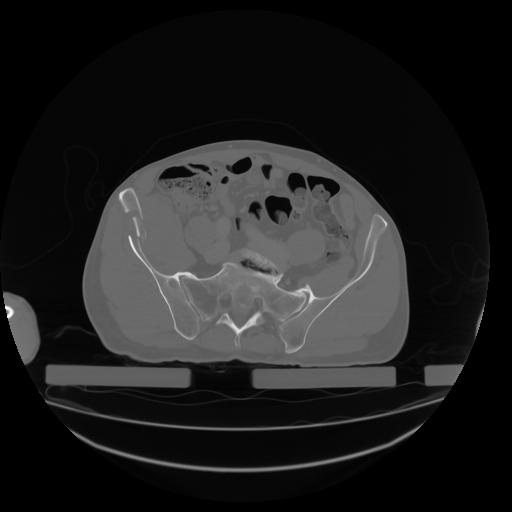

27 CUERPO,CE,Axial,3.0,CUERPO,,